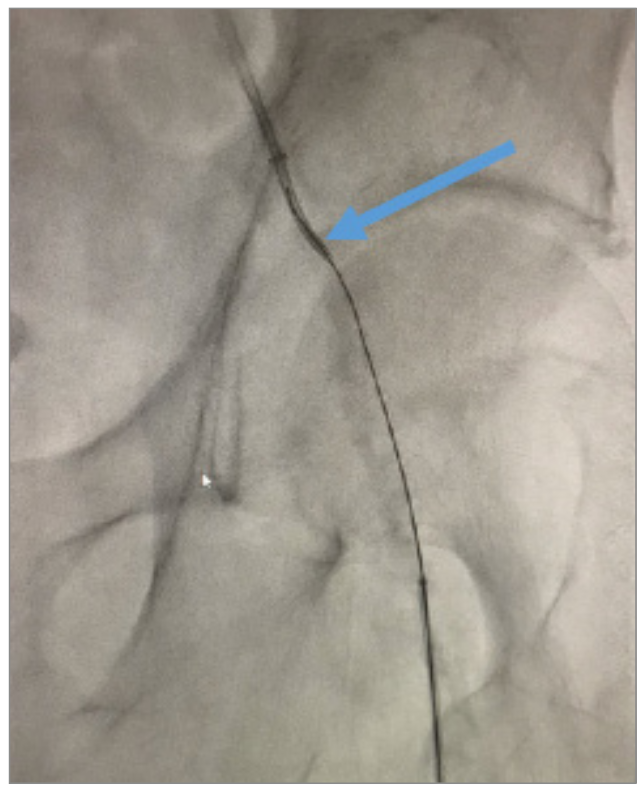

Angiography revealed that the superficial femoral artery (SFA) was occluded in the proximal segment with a short nub (Figure 1) and reconstituted in the mid segment by the profunda collaterals (Figure 2), before becoming reoccluded shortly thereafter and reconstituting in the distal SFA by the profunda collaterals (Figure 3). The P1 and P2 segments of the popliteal artery were patent, but the P3 segment had a short occlusion. The posterior tibial artery and peroneal artery also were patent.